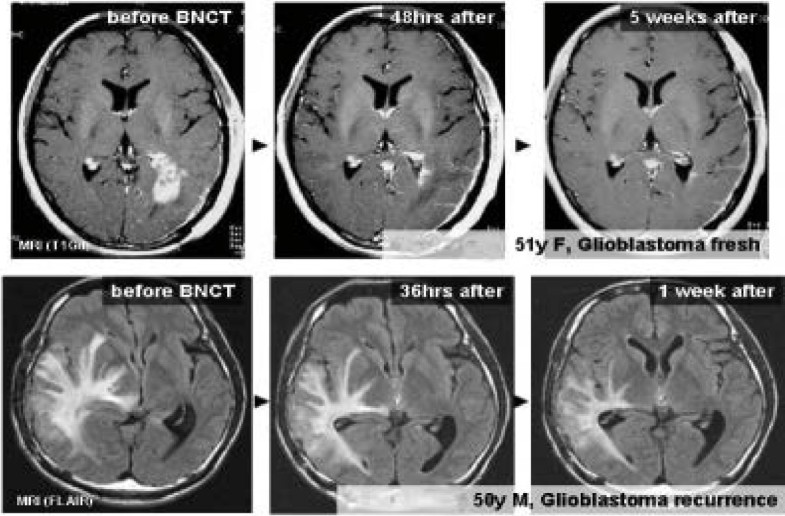

Figure 7

Radiographic changes following BNCT in two representative patients with GBM. In both, there was a reduction in both mass and peritumoral edema without the administration of corticosteroids or mannitol within a few days. This is also shown in the FLAIR image of Case #12.